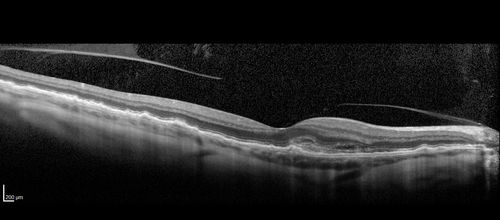

Late Onset Retinal Degeneration (L-ORD)

55 year old with acute vision loss from a CNVM in the right eye. He responded to Lucentis therapy. His mother and her family has been confirmed genetically to have L-ORD and were part of the early reports.